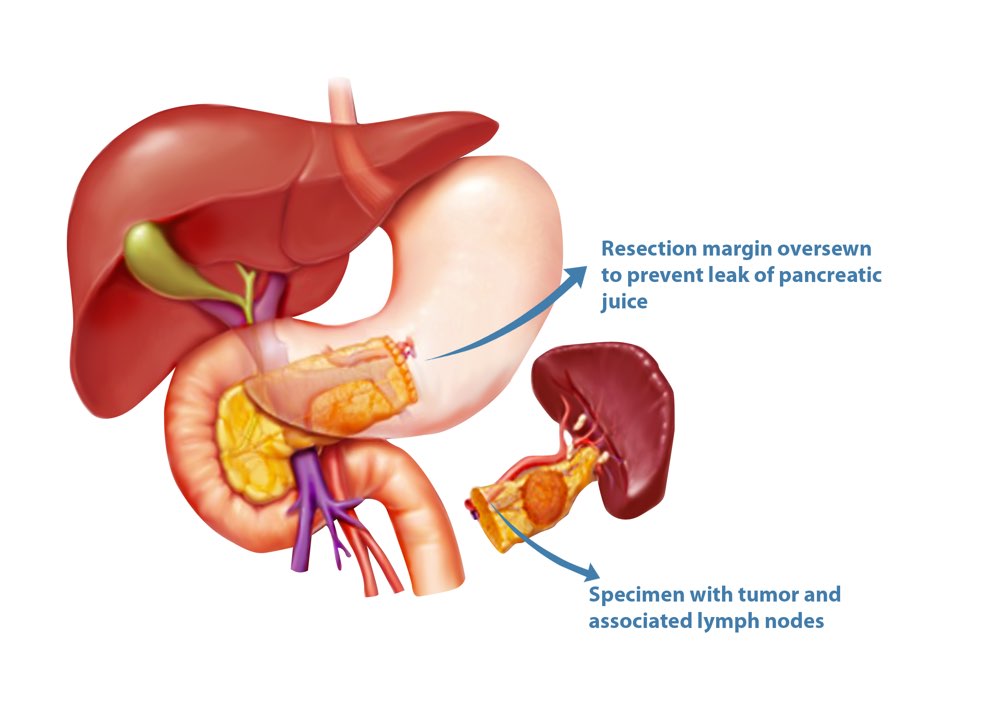

Фотографии медицинских исследований инсулиномы и синдрома Триады Уиппла